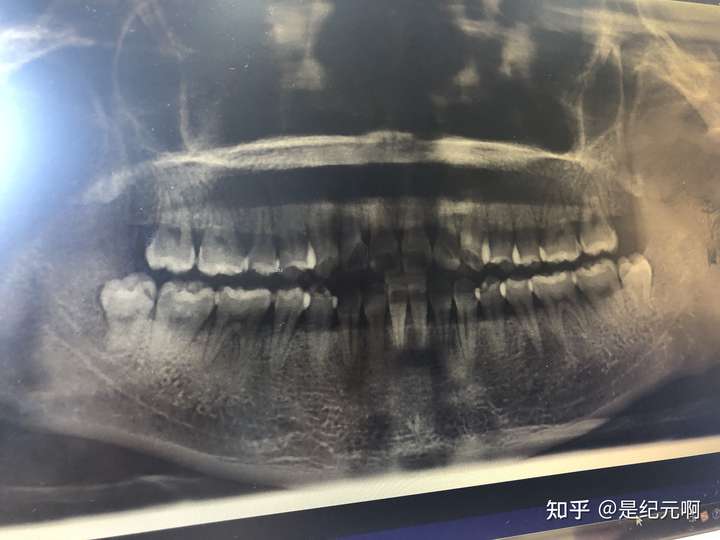

贴牙片,牙片图片

之前有点蛀牙拍的牙片.

贴牙片,昨天去洁牙.医生说要好好清理智齿~目前还没蛀牙

本组最厉害的牙片

先贴个牙片

牙痛,长了智齿,拍了个牙片——拔牙

全景牙片

智齿牙片